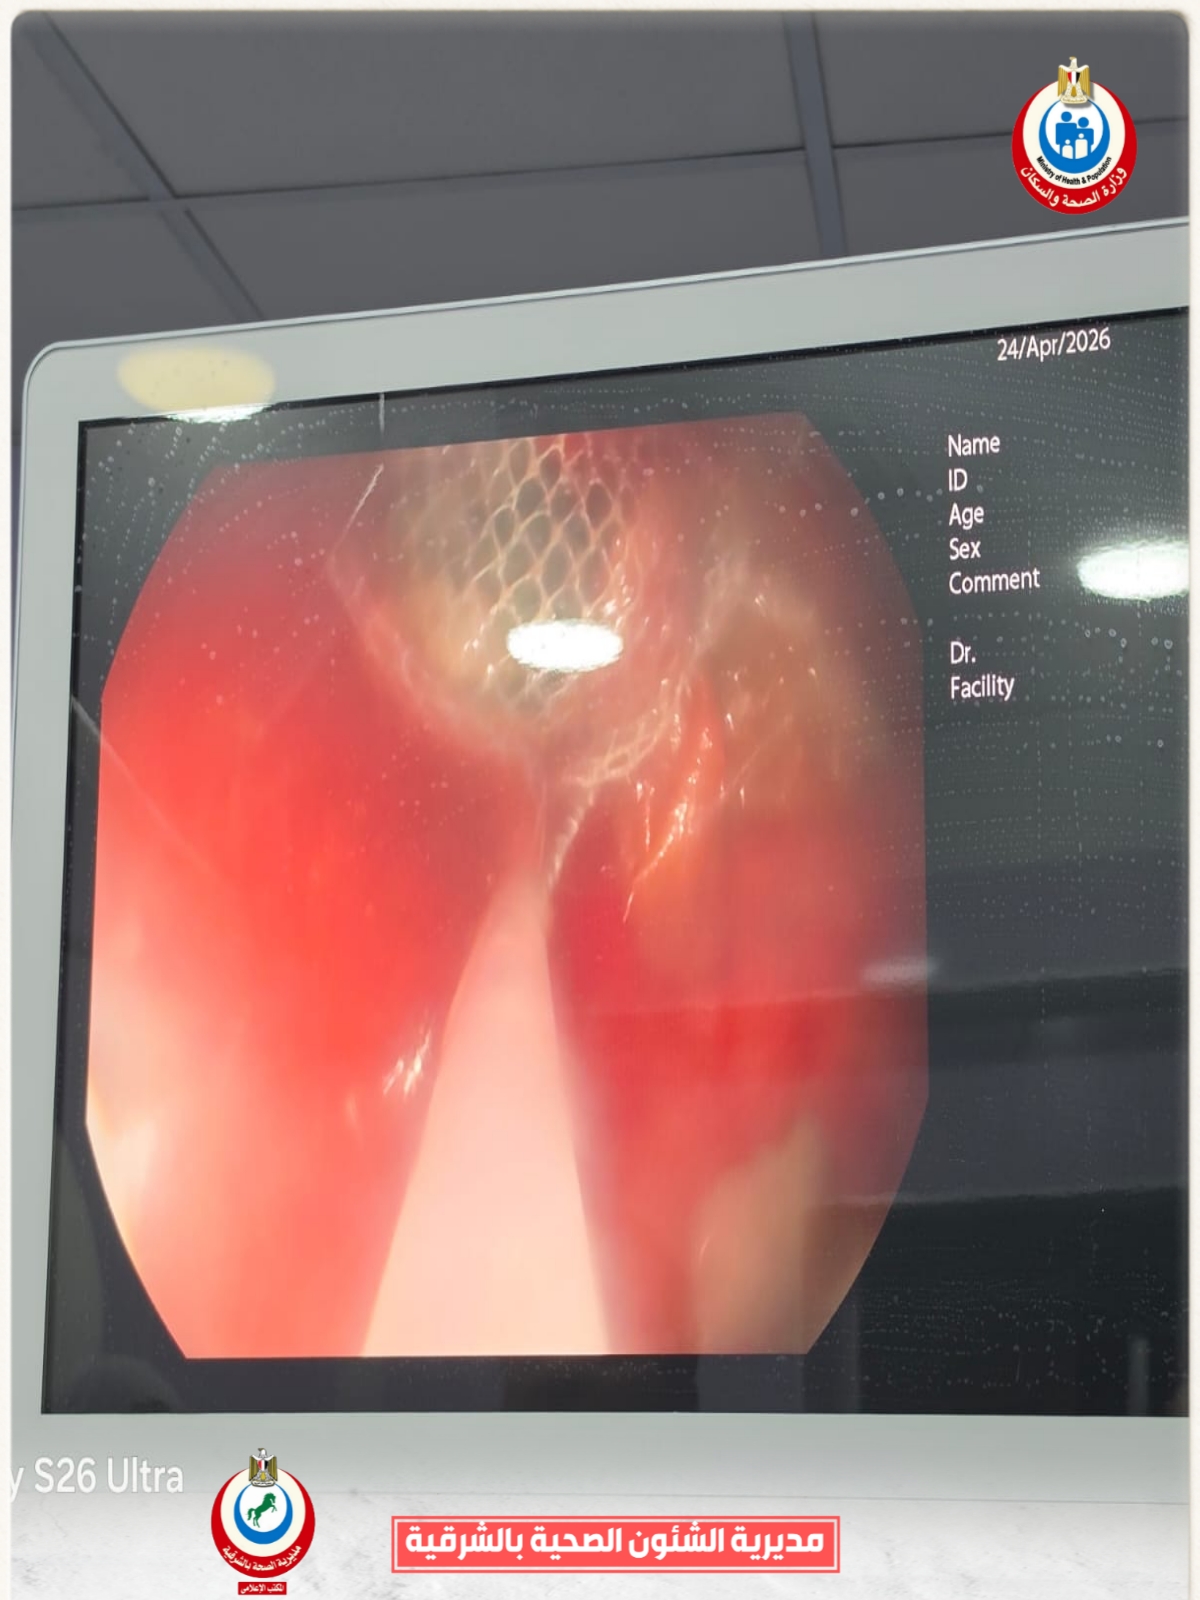

وأشار محمود عبدالفتاح مدير الإعلام والعلاقات العامة بالمديرية، إلى أنه فور استقبال الحالة، تم التنسيق الفوري من خلال مركز الخدمات الطارئة ١٣٧ بالمديرية، وتم تحويل الحالة إلى وحدة مناظير الجهاز الهضمي للأطفال، وإجراء كافة الفحوصات الطبية اللازمة لها، وإجراء منظار عاجل باستخدام التقنيات الحديثة، حيث نجح الفريق الطبي بفضل الله، في استخراج البطارية باستخدام شبكة المنظار، رغم صعوبة الحالة ووجود طعام داخل المعدة، وذلك مع الحفاظ على سلامة الأنسجة وعدم حدوث مضاعفات، وخرجت الطفلة بحالة عامة جيدة، وتحت الملاحظة الطبية للاطمئنان على استقرار حالتها.